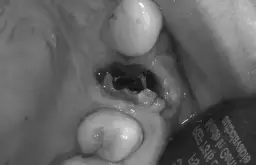

Stan zapalny zęba to reakcja obronna organizmu na infekcję bakteryjną, która najczęściej rozwija się w wyniku nieleczonej próchnicy. Bakterie, przedostając się przez uszkodzone szkliwo i zębinę, docierają do miazgi zęba tkanki zawierającej nerwy i naczynia krwionośne. Tam wywołują stan zapalny, który objawia się silnym bólem. Nieleczony, może prowadzić do martwicy miazgi, a następnie do rozprzestrzenienia się infekcji poza ząb, do otaczających tkanek, kości, a nawet do całego organizmu. To właśnie dlatego każdy stan zapalny zęba wymaga natychmiastowej uwagi.

- Wyciek ropy z dziąsła lub obecność przetoki ropnej.

Bagatelizowanie bólu zęba i nieleczona infekcja mogą prowadzić do bardzo poważnych, a nawet zagrażających życiu powikłań. Bakterie z zakażonego zęba mogą rozprzestrzenić się na sąsiednie tkanki, prowadząc do ropni okołowierzchołkowych, zapalenia kości szczęki lub żuchwy (osteomyelitis). W skrajnych przypadkach infekcja może przenieść się do odległych części ciała, wywołując ropnie mózgu, zapalenie wsierdzia czy sepsę. Z mojego doświadczenia wynika, że nie ma miejsca na zwłokę pilna wizyta u stomatologa jest jedynym sposobem na uniknięcie tych groźnych konsekwencji i skuteczne wyleczenie problemu u jego źródła.

- W przypadku obecności ropnia lub przetoki ropnej, zwłaszcza jeśli towarzyszy im ból i dyskomfort.